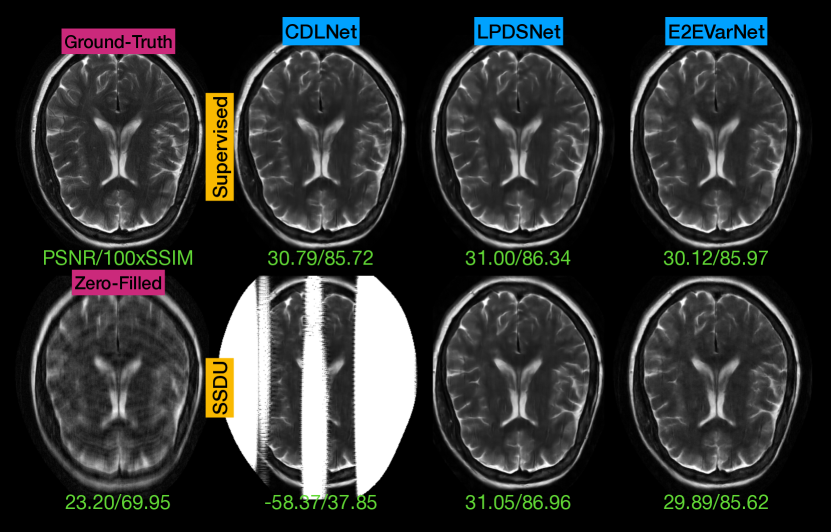

We first evaluate the performance of LPDSNet in the joint MRI reconstruction and denoising task. When trained with a supervised loss, LPDSNet achieves nearly a 2 dB increase in PSNR compared to the widely used E2EVarNet[10], while using orders of magnitude fewer parameters (Tbl.I, Fig.1). When using self-supervised training, CDLNet catastrophically fails to reconstruct images during inference (much lower PSNR compared to zero-filled, Tbl.I and Fig.1). This failure might be caused by the mismatch in mask sampling properties between training and inference, leading to numerical instability for CDLNet at inference time. In contrast, both LPDSNet and E2EVarNet remain stable in the SSDU scenario. Notably, LPDSNet trained with a self-supervised loss achieves the best performance (Tbl.I, Fig.1), slightly outperforming the supervised case. Note that self-supervision can enhance robustness against overfitting when limited noisy samples are available during training.

Figure 1: Visual comparison of models trained for 4×{4\times}4 × acceleration with σtrain=[0.04,0.06]superscript𝜎train0.040.06{\sigma^{\mathrm{train}}=[0.04,0.06]}italic_σ start_POSTSUPERSCRIPT roman_train end_POSTSUPERSCRIPT = [ 0.04 , 0.06 ], evaluated on a test-set slice with σtest=0.05superscript𝜎test0.05{\sigma^{\mathrm{test}}=0.05}italic_σ start_POSTSUPERSCRIPT roman_test end_POSTSUPERSCRIPT = 0.05. Magnitude images, clipped to max-value of 1, shown for display purposes. All inferences used the same fourier-space mask and noise realization. Note that CDLNet’s catastrophic failure doesn’t happen for every sample, but happens for a large proportion, such as shown above.